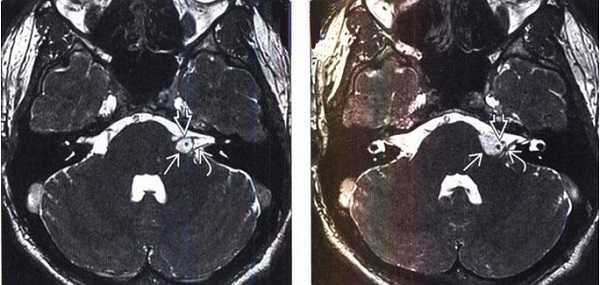

МРТ головного мозга. На мрт в аксиальной плоскости отмечается объемное образование внутреннего слухового прохода слева (стрелка), с четкими и неровными контурами, деформирующее окружающие структуры. После внутривенного введения парамагнитного контрастного вещества отмечается интенсивное и неоднородное его накопление образованием (изображение справа) — невринома.

МРТ головного мозга. Т1-взвешенная аксиальная МРТ (фрагмент). Мосто-мозжечковые углы в норме. Цветовая обработка изображения.

Мосто-мозжечковый угол (ММУ) - это стык Варолиева моста, продолговатого мозга и мозжечка. Основным поводом к исследованию этой области является сенсоневральная тугоухость. ЛОР методы позволяют сузить поиск, определив, что что тугоухость связана с поражением нерва ретрокохлеарно ( в ММУ, а не в ухе), либо в структурах уха. В последнем случае применяется чаще КТ. МРТ СПб позволяет выбирать место выполнения МРТ, мы рекомендуем Вам обследоваться у нас, где возмлжности прицельного исследования больше, чем во многих других МРТ центрах. При МРТ в СПб в наших центрах при ретрокохлеарной тугоухости методом выбора служит МРТ головного мозга, так как поражается 8 черепной нерв (преддверно-улитковый).

Типичные опухоли этой области невриномы (шванномы) и менингиомы. При невриномах может быть фрагмент опухоли во внутреннем слуховом проходе, что видно, особенно при МРТ головного мозга с контрастированием.

Вестибулокохлеарный нерв (VIII) состоит из 4 пучков. Опухоли происходят обычно из вестибулярной его части. Шваннома - инкапсулированная доброкачественная (градация 1) опухоль, происходящая из дифференцированных неопластических шванновских клеток оболочек периферических нервов. Невриномы ММУ составляют около 3% опухолей головного мозга. Часть шванном (двухсторонние слуховых нервов) связана с НФ 2 типа. Пик частоты между 40 и 60 годами. Растут медленно и крайне редко малигнизируются. Клинические проявления связаны с нарушением функции нерва и компрессией ствола. Шваннома может происходить из любого отрезка по ходу нерва и хорошо прослеживается при МРТ области ММУ. Невринома видна как на Т2-взвешенных, так и на Т1-взвешенных МРТ в виде округлого образования. Невриномы хорошо и равномерно усиливаются после МРТ с введением контрастного вещества. Невриномы области цистерны могут иметь компонент во внутреннем слуховом проходе, особенно, хорошо видимый при МРТ головного мозга с контрастированием. Изредка встречаются невриномы полностью расположенные внутри канальца. Они составляют наибольшую диагностическую сложность при МРТ, требуют тонких срезов и контрастирования. Менингиомы ММУ обычно типично расположены и при МРТ имеют характерную форму и типичные черты при МРТ с контрастированием. Однако редко встречаются внутриканальцевые менингиомы. При МРТ они неотличимы от неврином. Холестеатомы при МРТ имеют смешанную интенсивность сигнала, в зависимости от их содержимого. На диффузионно-взвешенных МРТ холестеатомы обычно яркие.